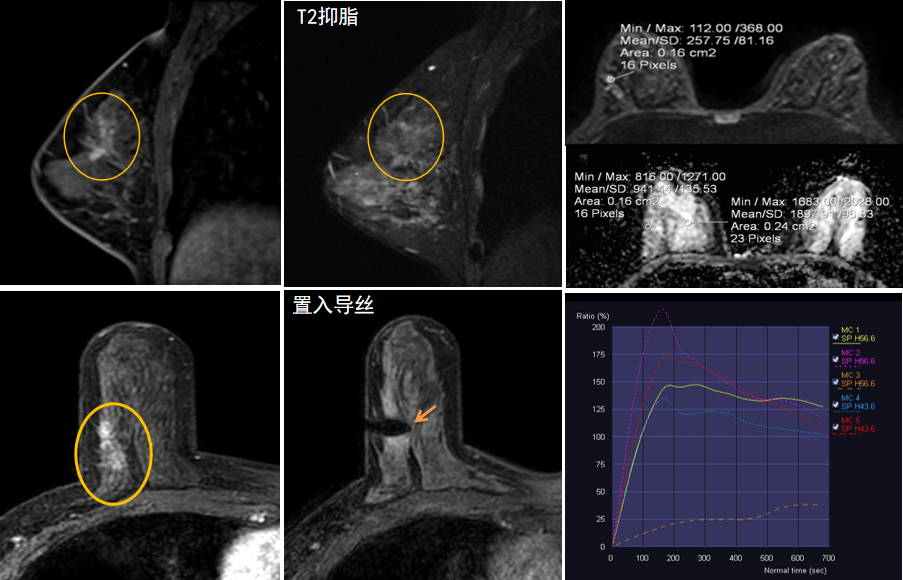

今年45歲的某女士,兩個月前行超聲檢查發(fā)現(xiàn)右乳結(jié)節(jié),乳腺X線攝影檢查提示右乳外上象限局部腺體結(jié)構(gòu)扭曲并簇狀無定形鈣化,為了進一步評估病變性質(zhì)并確定范圍進行了乳腺MR平掃 DWI 增強的檢查,經(jīng)MR評估發(fā)現(xiàn)右乳病變范圍較廣,評估為BI-RADS 4類可疑病變,需要取得病理學結(jié)果。

只能借助影像學引導,但超聲僅顯示了病變中的小結(jié)節(jié),X線攝影(鉬靶)顯示的病變邊界比較模糊,要想做到精準完整切除必須借助MR的引導,而這一技術(shù)對軟硬件平臺及人員技術(shù)都有很高的要求,因此,多年來一直是我國乳腺病變診療的盲區(qū),經(jīng)常是MR發(fā)現(xiàn)可疑病變但卻無法處理。目前全國僅有少數(shù)幾家醫(yī)院開展了這方面的部分工作。

西安國際醫(yī)學中心醫(yī)院影像診療中心陳寶瑩主任團隊有著十余年影像引導下乳腺介入診療的經(jīng)驗,借助醫(yī)院高精尖的MR平臺,成為西北首個全面展開MR引導下各項乳腺介入診療技術(shù)的團隊,能夠?qū)Τ暭叭橄賆線無法顯示或顯示不清的病變進行MR引導下的導絲定位、穿刺活檢及真空輔助旋切。

陳寶瑩主任及其帶領(lǐng)的MR介入診療小組詳細詢問了病情,分析了患者資料,并與患者和臨床醫(yī)生進行了充分溝通,確定于手術(shù)前為患者實施MR引導下的病變穿刺導絲定位和體表范圍確定。手術(shù)前陳寶瑩主任帶領(lǐng)聶品醫(yī)師、馬小偉技師、韓愛萍護士長等MR介入診療小組成員,借助MR高清的圖像顯示和定位系統(tǒng),確定病變范圍,精準穿刺置入定位導絲,并準確標記出病變體表范圍,整個過程患者無任何不適。在定位導絲和體表范圍標記的輔助下,甲乳外科劉曉敏主任精準切除了病變,解除了患者的后顧之憂。

國內(nèi)外指南均建議40歲以上的女性每年行一次雙乳X線攝影(鉬靶)檢查,以篩查乳腺癌。對于乳腺癌高危人群40歲以前即建議開始乳腺癌篩查,除了進行乳腺X線攝影(鉬靶)篩查外需要補充MR檢查,MR檢查敏感性最高,能夠發(fā)現(xiàn)大量X線攝影和超聲檢查陰性的可疑病變,基于多模態(tài)、多參數(shù)的結(jié)構(gòu)和功能成像的基礎(chǔ)上,MR能夠精準顯示病變位置、范圍以及病變內(nèi)的活性區(qū)域,MR引導下的介入診療不但解決了僅在MR顯示的病變的處置難題,而且能夠精準定位活性區(qū)域,保證了定位、活檢及旋切的準確性。